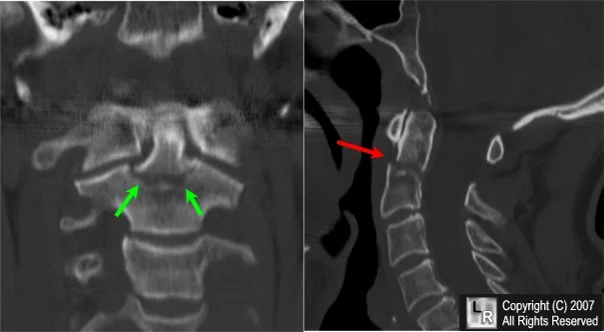

Advanced Imaging

- CT Scan:

- In complex and intra-articular fractures

- In spine

- In pelvic and acetabular fractures

- In calcaneal fractures